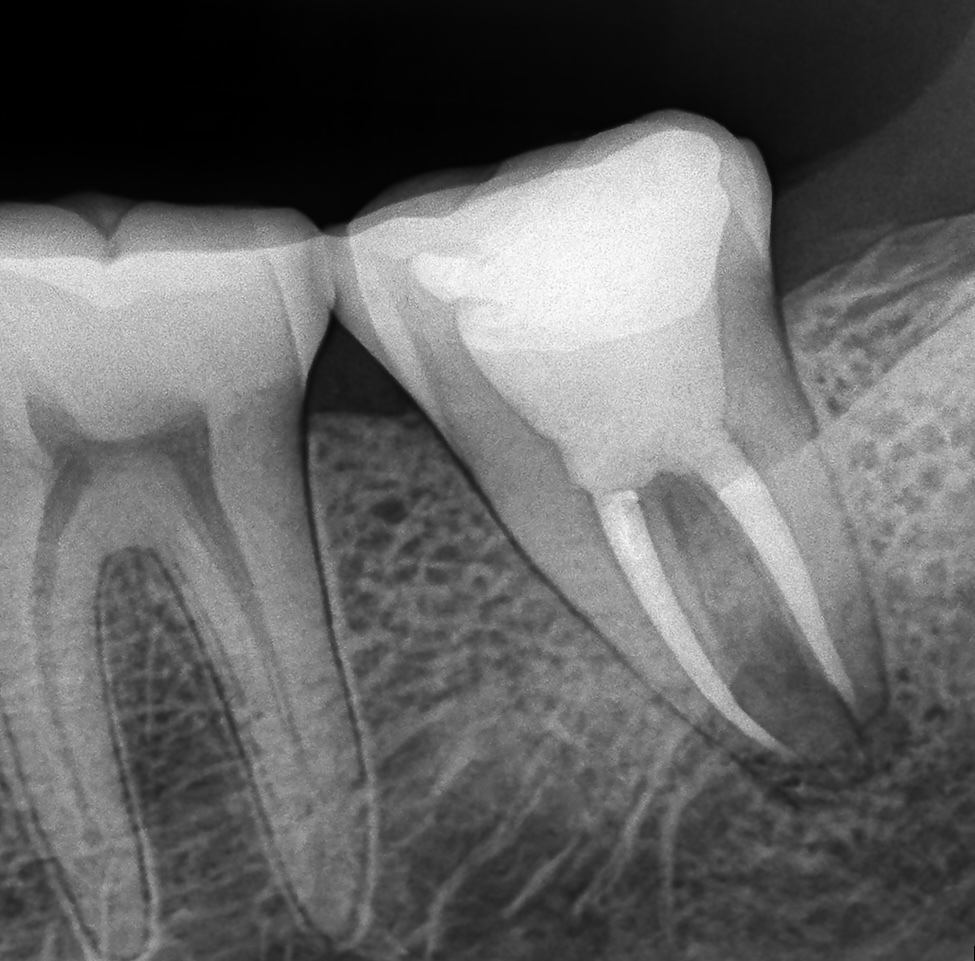

Post-operative radiographs demonstrated excellent obturation density and apical seal. The patient remained asymptomatic at review, with periapical healing evident radiographically after follow-up.

- Fig 5. Post-operative radiograph demonstrating apical seal.